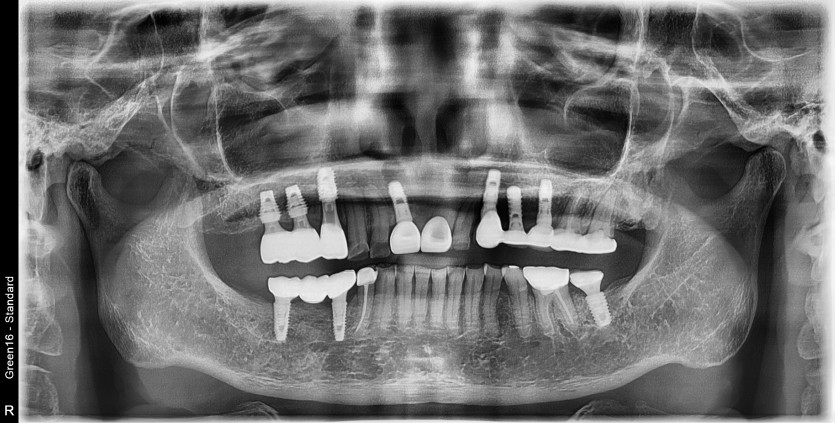

타원임플란트 #14 파절되어 재수술